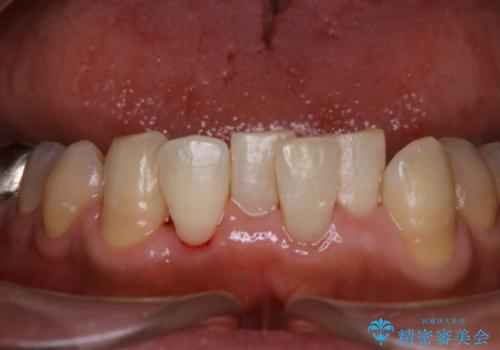

50代男性 1年ぶりにPMTC 前歯をきれいに

- 1年ぶりの来院だが30分コースで前歯だけ綺麗にクリーニングしてほしいとのことでした。

PMTC30分コースで前歯メインにクリーニングを行いました。